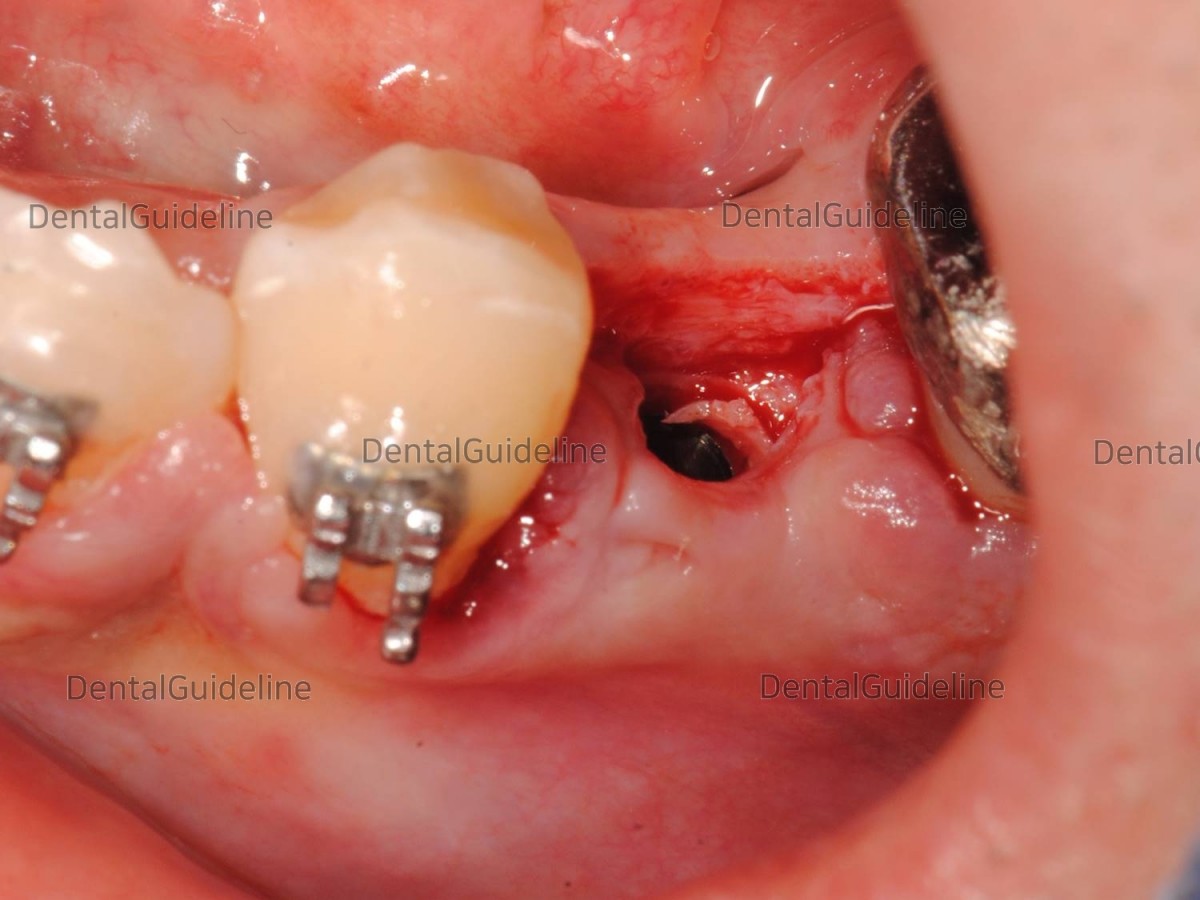

For the Healing Abutment engagement, soft tissue trimming was needed.

Soft tissue trimming with a tissue punching tool.

After tissue punching.